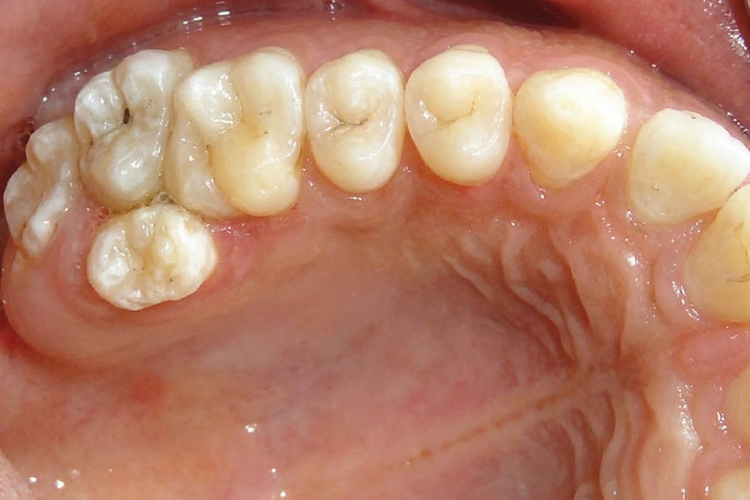

Intraoral photograph showing the upper dental arch with an extra molar.

Intraoral view showing a paramolar supernumerary tooth beside the molars.

Paramolar Develops beside or between the molars at the back of the mouth, usually on the cheek-facing side of the molar teeth.